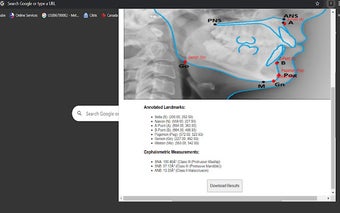

측면 두개골 분석은 치과 전문가와 학생을 위해 맞춤화된 Chrome 확장 프로그램으로, 측면 두개골 추적 및 분석에 대한 간소화된 접근 방식을 제공합니다. 이 도구는 사용자가 측면 두개골 사진을 업로드할 수 있게 하여 Sella, Nasion 및 A-Point와 같은 필수 해부학적 랜드마크의 정확한 수동 추적을 가능하게 합니다. 사용자 친화적인 인터페이스를 통해 초보자와 경험이 풍부한 교정 전문의 모두가 접근할 수 있도록 추적 과정을 용이하게 합니다.

수동 추적 외에도 이 확장 프로그램은 SNA, SNB 및 ANB 각도를 포함한 중요한 두개골 측정값을 자동으로 계산합니다. 사용자는 분석 결과를 검토하고 저장하며 편리한 형식으로 내보낼 수 있어 임상 평가 및 연구의 효율성을 향상시킵니다. 이 확장 프로그램은 교정학이나 치과 교육에 참여하는 모든 사람에게 귀중한 자원으로, 정확하고 신뢰할 수 있는 결과를 쉽게 제공합니다.